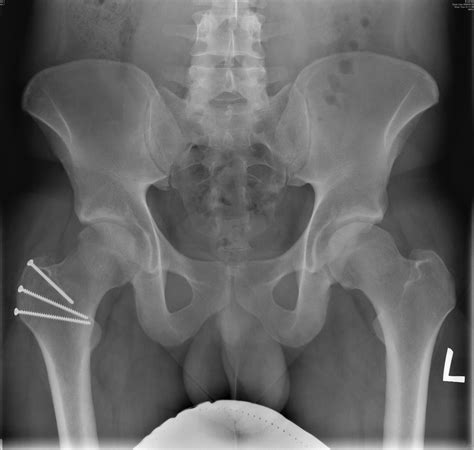

For younger patients or active adults who still have healthy cartilage, the Periacetabular Osteotomy (PAO) is often the gold standard. During this procedure, the surgeon cuts the pelvic bone around the socket to reposition it into a more stable orientation. The bone is then secured with metal screws. This surgery is highly effective at correcting the anatomy to prevent future arthritis.